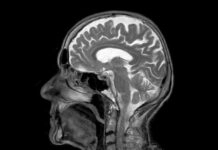

5-ALA: Η νέα εποχή στη χειρουργική των όγκων του εγκεφάλου

Γράφει ο Δρ. Νικόλαος ΚαραγεώργοςΔιευθυντής Νευροχειρουργικής, Ιατρικό Κέντρο Αθηνών (Μαρούσι)Πιστοποιημένος στη χειρουργική αφαίρεση όγκων εγκεφάλου με χρήση φθορισμού μέσω 5-ALAwww.neurosurgeon-athens.grΔρ. Νικόλαος Καραγεώργος Διευθυντής Νευροχειρουργικής,...